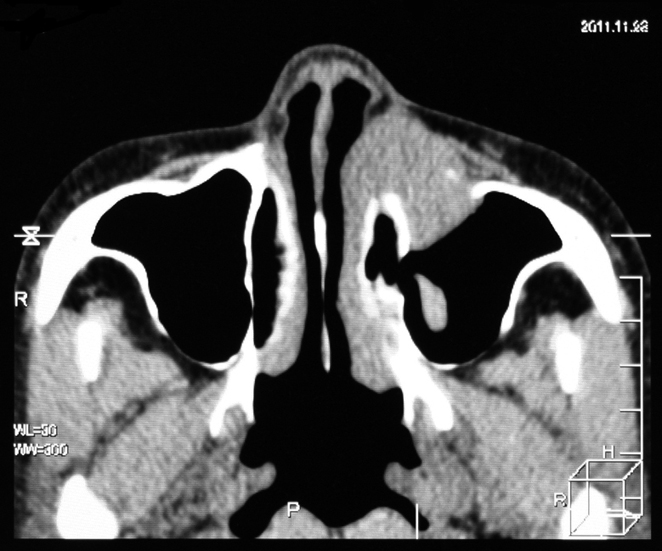

extramedullary plasmacytoma arising in the sinonasal tract

71year old, male